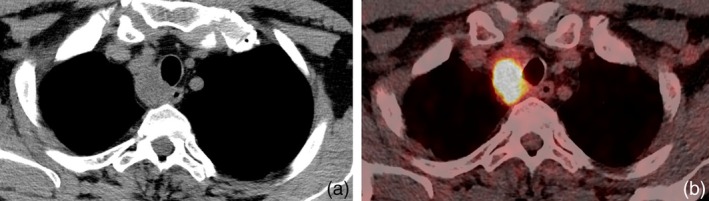

矽肺病是一种重要的职业病,由吸入二氧化硅引起,可导致肺部炎症和纤维化。矽肺可误诊为恶性疾病,因为两者在FDG-PET成像上均可表现为高代谢病变。本病例系列描述了3例基于FDG-PET检查结果怀疑有原发性肺恶性肿瘤的患者,但发现有肺矽肺病。通过这个系列,我们展示了组织学检查如何区分矽肺和恶性肿瘤,并提供建议,以帮助临床医生区分这两种疾病。

Silicosis, an important occupational disease, is caused by inhalation of silicon dioxide and can lead to pulmonary inflammation and fibrosis. Silicosis can be misdiagnosed for malignant disease, as both can present with hypermetabolic lesions on FDG-PET imaging. This case series describes three patients who were suspected to have a primary lung malignancy based on FDG-PET findings, but were found to have pulmonary silicosis. With this series, we demonstrate how histologic examination can differentiate between silicosis and malignancy and provide suggestions to help clinicians differentiate between these two illnesses.